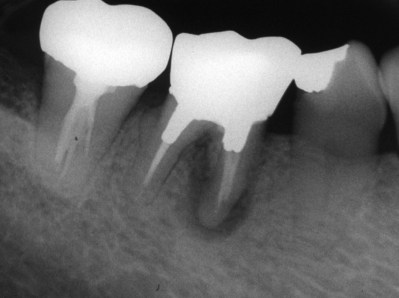

歯根破折

垂直性歯根破折が疑われる下顎右側第一大臼歯のエックス線写真を別に示す。診断に有用なのはどれか。1つ選べ。